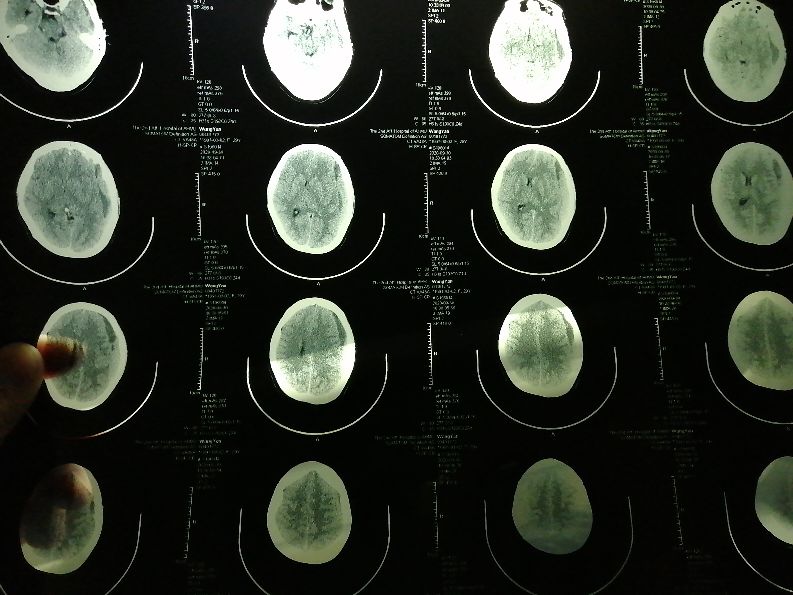

所以恳请大家有知道的帮帮忙,怎么处理这种情况。我就感觉医生可能有问题,我们都是正常产检的,都没有问题,做了核磁共振脑部也正常,也没有医生说的血管瘤等病变因素,什么凝血功能也查了,都正常。我就是想请院方给个致病原因,这都十天了也没给个回复!我老婆现在视力越来越差了,我越来越担心老婆的身体,我在想有可能也是那个时候生产引起的。我就想如果是医生的责任怎么处理。昨天刚做的CT,今早查房医生说血水减少了一点,可以吃点药在观察观察,好的话不做手术,看着老婆不那么心塞了,可我却无法控制住自己愤怒的心情!!!我终于知道医闹怎么出现的!逼急了大家都不好受!

10月7日CT结果